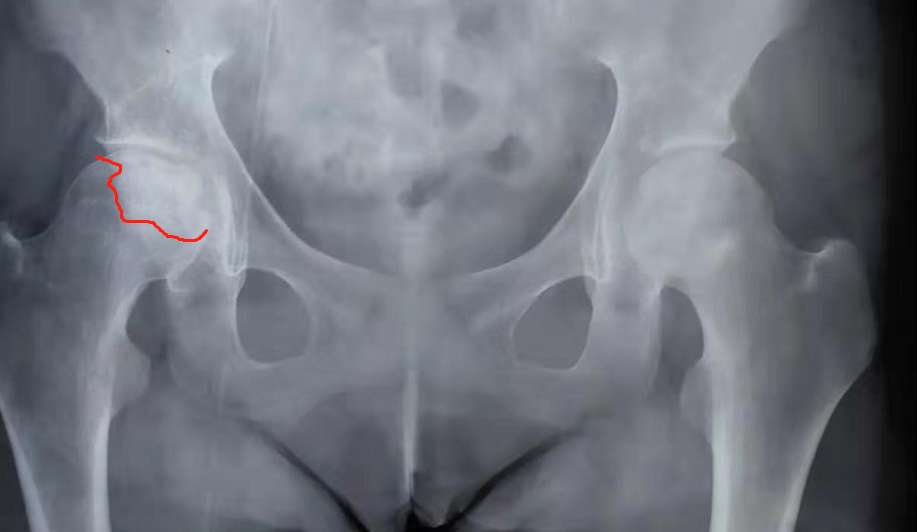

我才吃一年半激素,也双侧骨坏了。拍DR看不出来,复查再拍磁共振才看到。